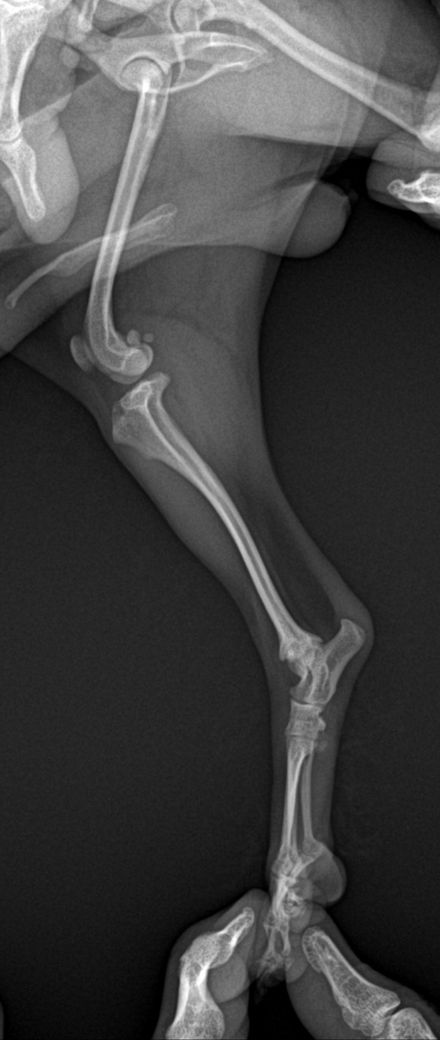

담당 의사선생님께서 십자인대의 문제는 확인이 어렵다고 하셨는데, 보통 X-ray로 확인하지 않나요..?ㅠㅠ 그래서 아하에 계시는 수의사 분들께 병원에서 받아온 X-ray 사진과 병원에 진료 후 내려놨을 때 걷는 영상을 첨부하오니, 100%가아니더라도 십자 인대 수술이 필요해보이는지, 다른 소견은 없는지 등의 진단을 부탁드립니다..!ㅠㅠ

30cm가 이니라 10여도 터질 십자인대는 터집니다. 다만 첨부한 사진에서 양쪽 뒷다리의 측면 사진이 모두 첨부되어야 관절낭을 중심으로 비교 평가할 수 있는데 사진이 누락되어 판단할 수 없습니다. 다만 주관적으로 2번째 첨부 사진에서 아킬레스건의 부종 양상이 관찰되고 슬개골 관절낭의 심한 종창은 보이지 않아 십자인대 단열보다는 아킬레스건 부분단열을 먼저 고려해야 할것으로 보입니다. 주치의의 지시에 따라 평가 진행해도 크게 무방합니다.